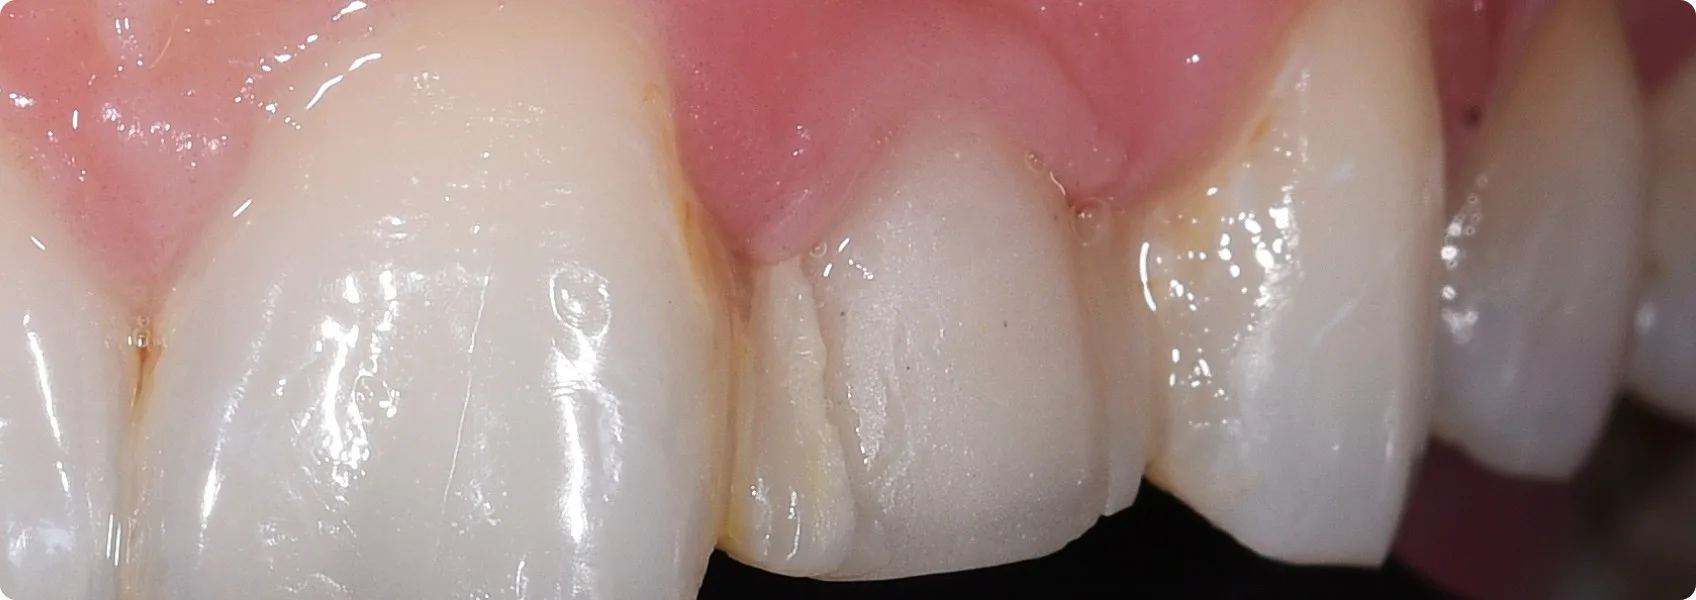

Mimo dorosłego wieku, u Pacjentki przetrwał ząb mleczny w pozycji siekacza bocznego — górnej dwójki.

Ząb mleczny jest mniejszy niż jego stały odpowiednik. Miejsca na uzupełnienie protetyczne jest mniej, a dziąsło wokół takiego zęba często znajduje się niżej niż powinno. To sprawia, że po założeniu licówki linia dziąseł nie będzie równa, a w uśmiechu pojawi się asymetria.

Aby wyrównać linię dziąseł, Pacjentka przeszła gingiwektomię — zabieg chirurgiczny polegający na usunięciu fragmentu dziąsła.

Nawet najładniejsze licówki nie będą wyglądać dobrze przy nieregularnej i asymetrycznej girlandzie dziąsłowej. Gingiwektomia pozwala wyrównać wysokość dziąseł, żeby licówki miały symetryczne podstawy, a cały uśmiech wyglądał naturalnie i proporcjonalnie.